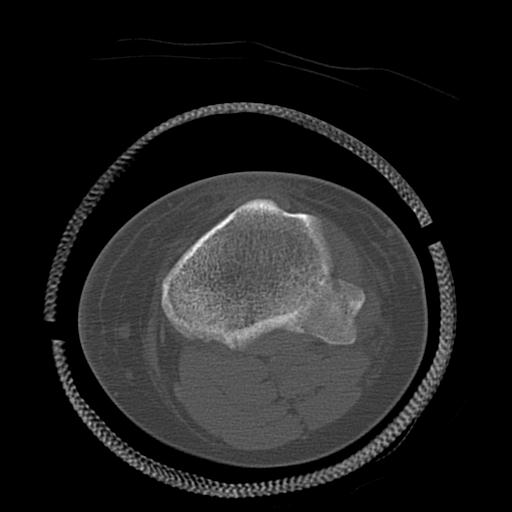

49554 3/13 膝 4R 3/16 4R 1/18 2R 78歳男性 膝蓋骨骨折